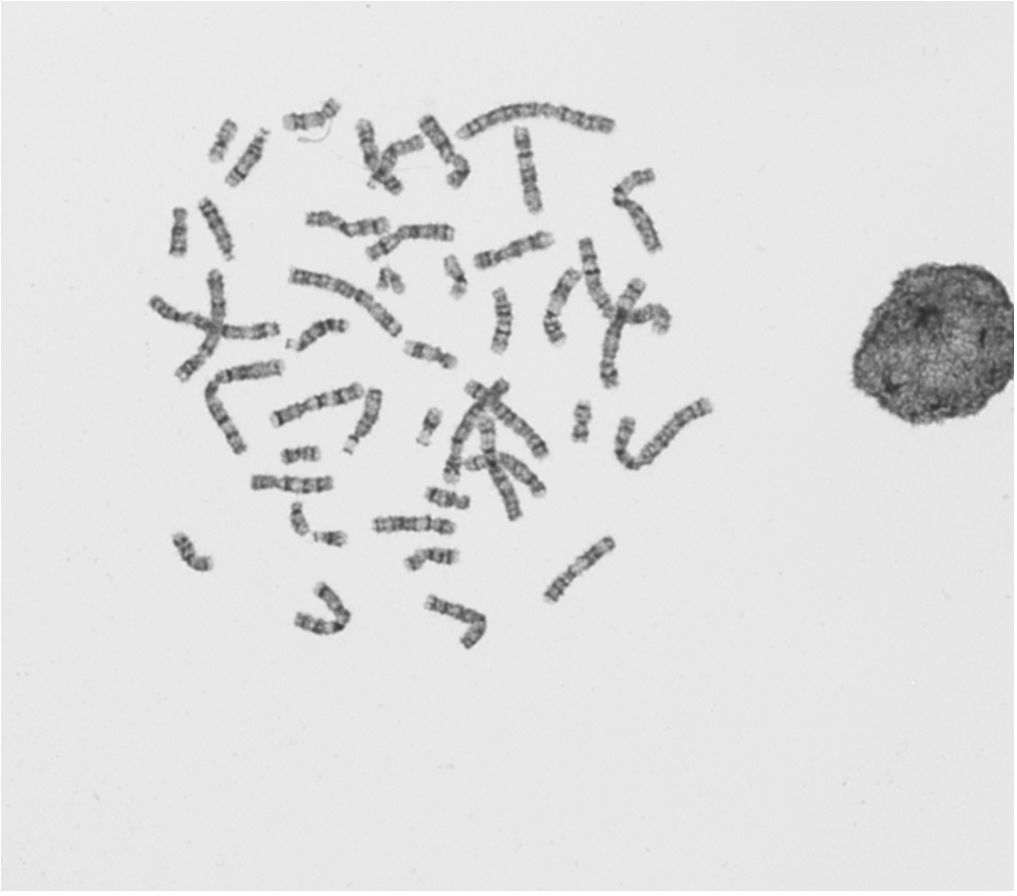

EEQ_SG_2019-GTG-01.JPG

EEQ_SG_2019-GTG-01.JPG (49.95 Kio) Vu 53454 fois